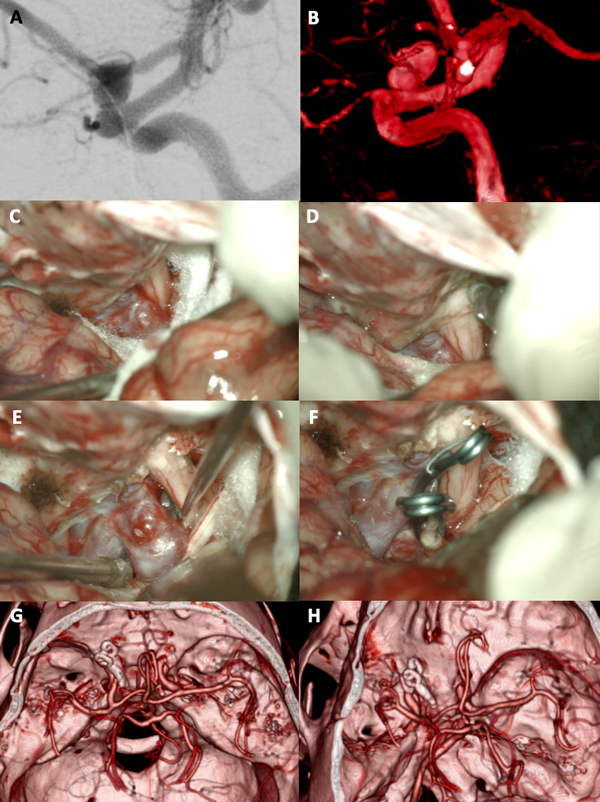

Figura 7. A-B: Se aprecia una arteriografía cerebral que evidencia un aneurisma carótido oftálmico izquierdo gigante. Es notoria la presencia de una ampolla (“bleb”) de gran tamaño. C-F: Fotografías intraoperatorias. Observamos la cisterna óptico-carotidea donde es visible el saco aneurismático. Dado el tamaño de la lesión se realiza una clinoidectomía anterior total y sección del anillo dural distal logrando una adecuada exposición del cuello del aneurisma. Se muestra la exclusión del aneurisma con múltiples clips. G-H: Imágenes de arteriografía cerebral post operatoria que evidencia la exclusión completa del aneurisma con preservación de la arteria oftálmica.